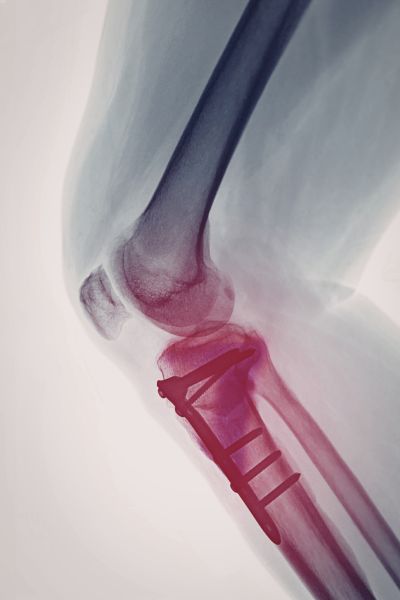

Dr S R Panda is a reputed orthopaedic surgeon in Kolkata offering advanced facilities including General & Joint Replacement OT, Arthroscopy & Trauma OT, and Spine Surgery & Sports Injury OT, ensuring precise diagnosis, modern surgical techniques, and comprehensive bone and joint care under one roof.

Arthroscopy & Trauma OT